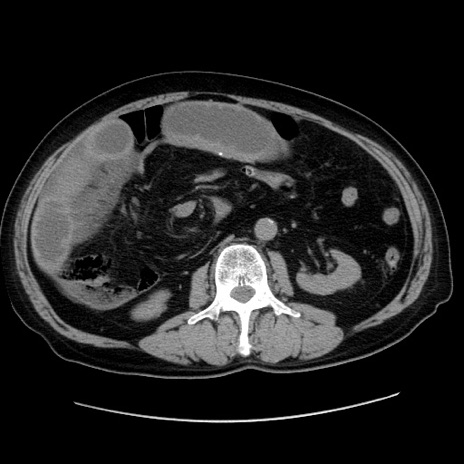

冠状断像

【症例】80歳代男性

【主訴】臍周囲痛

【現病歴】約6時間前から臍下部痛が出現。次第に腹部膨隆・背部痛も生じてきたため来院。背部痛の場所は変化しない。

【身体所見】意識清明、BT 36.3℃、BP  131/87mmHg、P 87bpm、SpO2 100%(RA)、臍周囲自発痛・圧痛あり、反跳痛なし、自発痛部位に一致して板状硬あり、腹部膨隆、腸雑音減弱、CVA tenderness両側陰性。